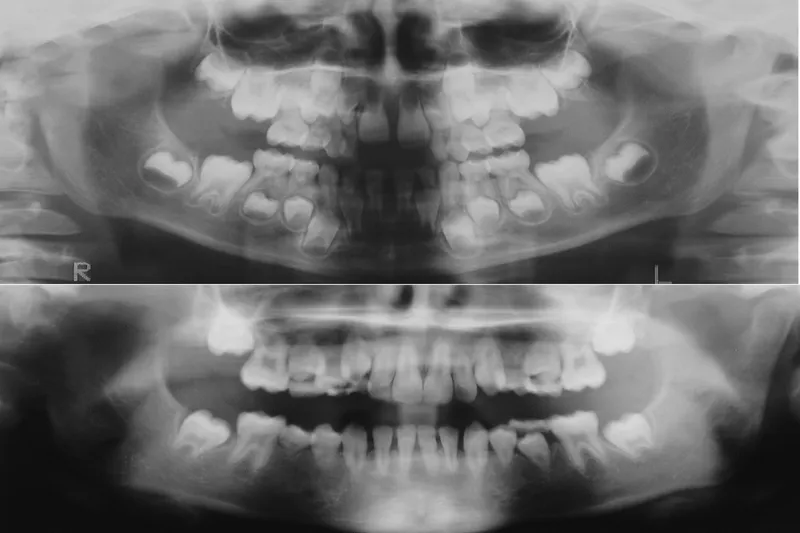

a760 fig.